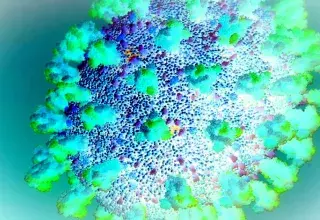

Virus Nipah en Inde : cinq cas confirmés, une centaine de personnes en quarantaine

L'Inde est confrontée à sa septième épidémie de virus Nipah, avec cinq cas confirmés au Bengale occidental depuis le 12 janvier 2026. Les autorités sanitaires indiennes ont placé p...